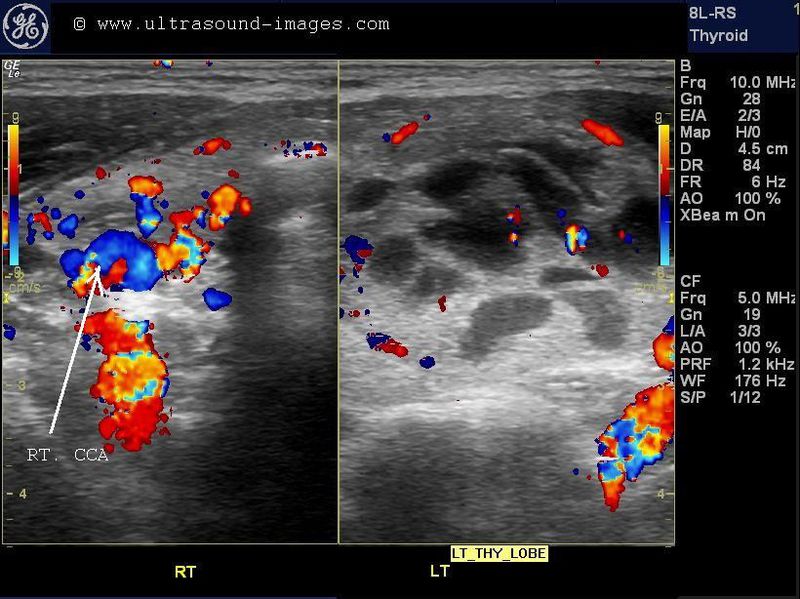

densely calcific colloid nodule

This young adult male patient complained of discomfort in the left side of the neck. Sonography detected this colloid nodule in the upper half of the left lobe of the thyroid. Ultrasound images show a densely calcific colloid nodule of 2 x 1 cms. in the left lobe thyroid. Color Doppler ultrasound shows typical twinkling artefacts in this calcific colloid nodule of the thyroid. FNAC was advised and would show a classic gritty feel as the needle traverses this densely calcific lesion. Such thyroid lesions are highly likely to be benign due to the presence of macro-calcification and other characterisitic such as well defined margins of this calcific thyroid lesion.